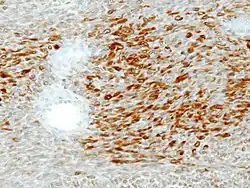

Description de cette image, également commentée ci-après

Adénome pléomorphe avec composante cellulaire épithéliales à gauche et conjonctive à droite.

Immunohistochimie

Immunohistochimie S-100